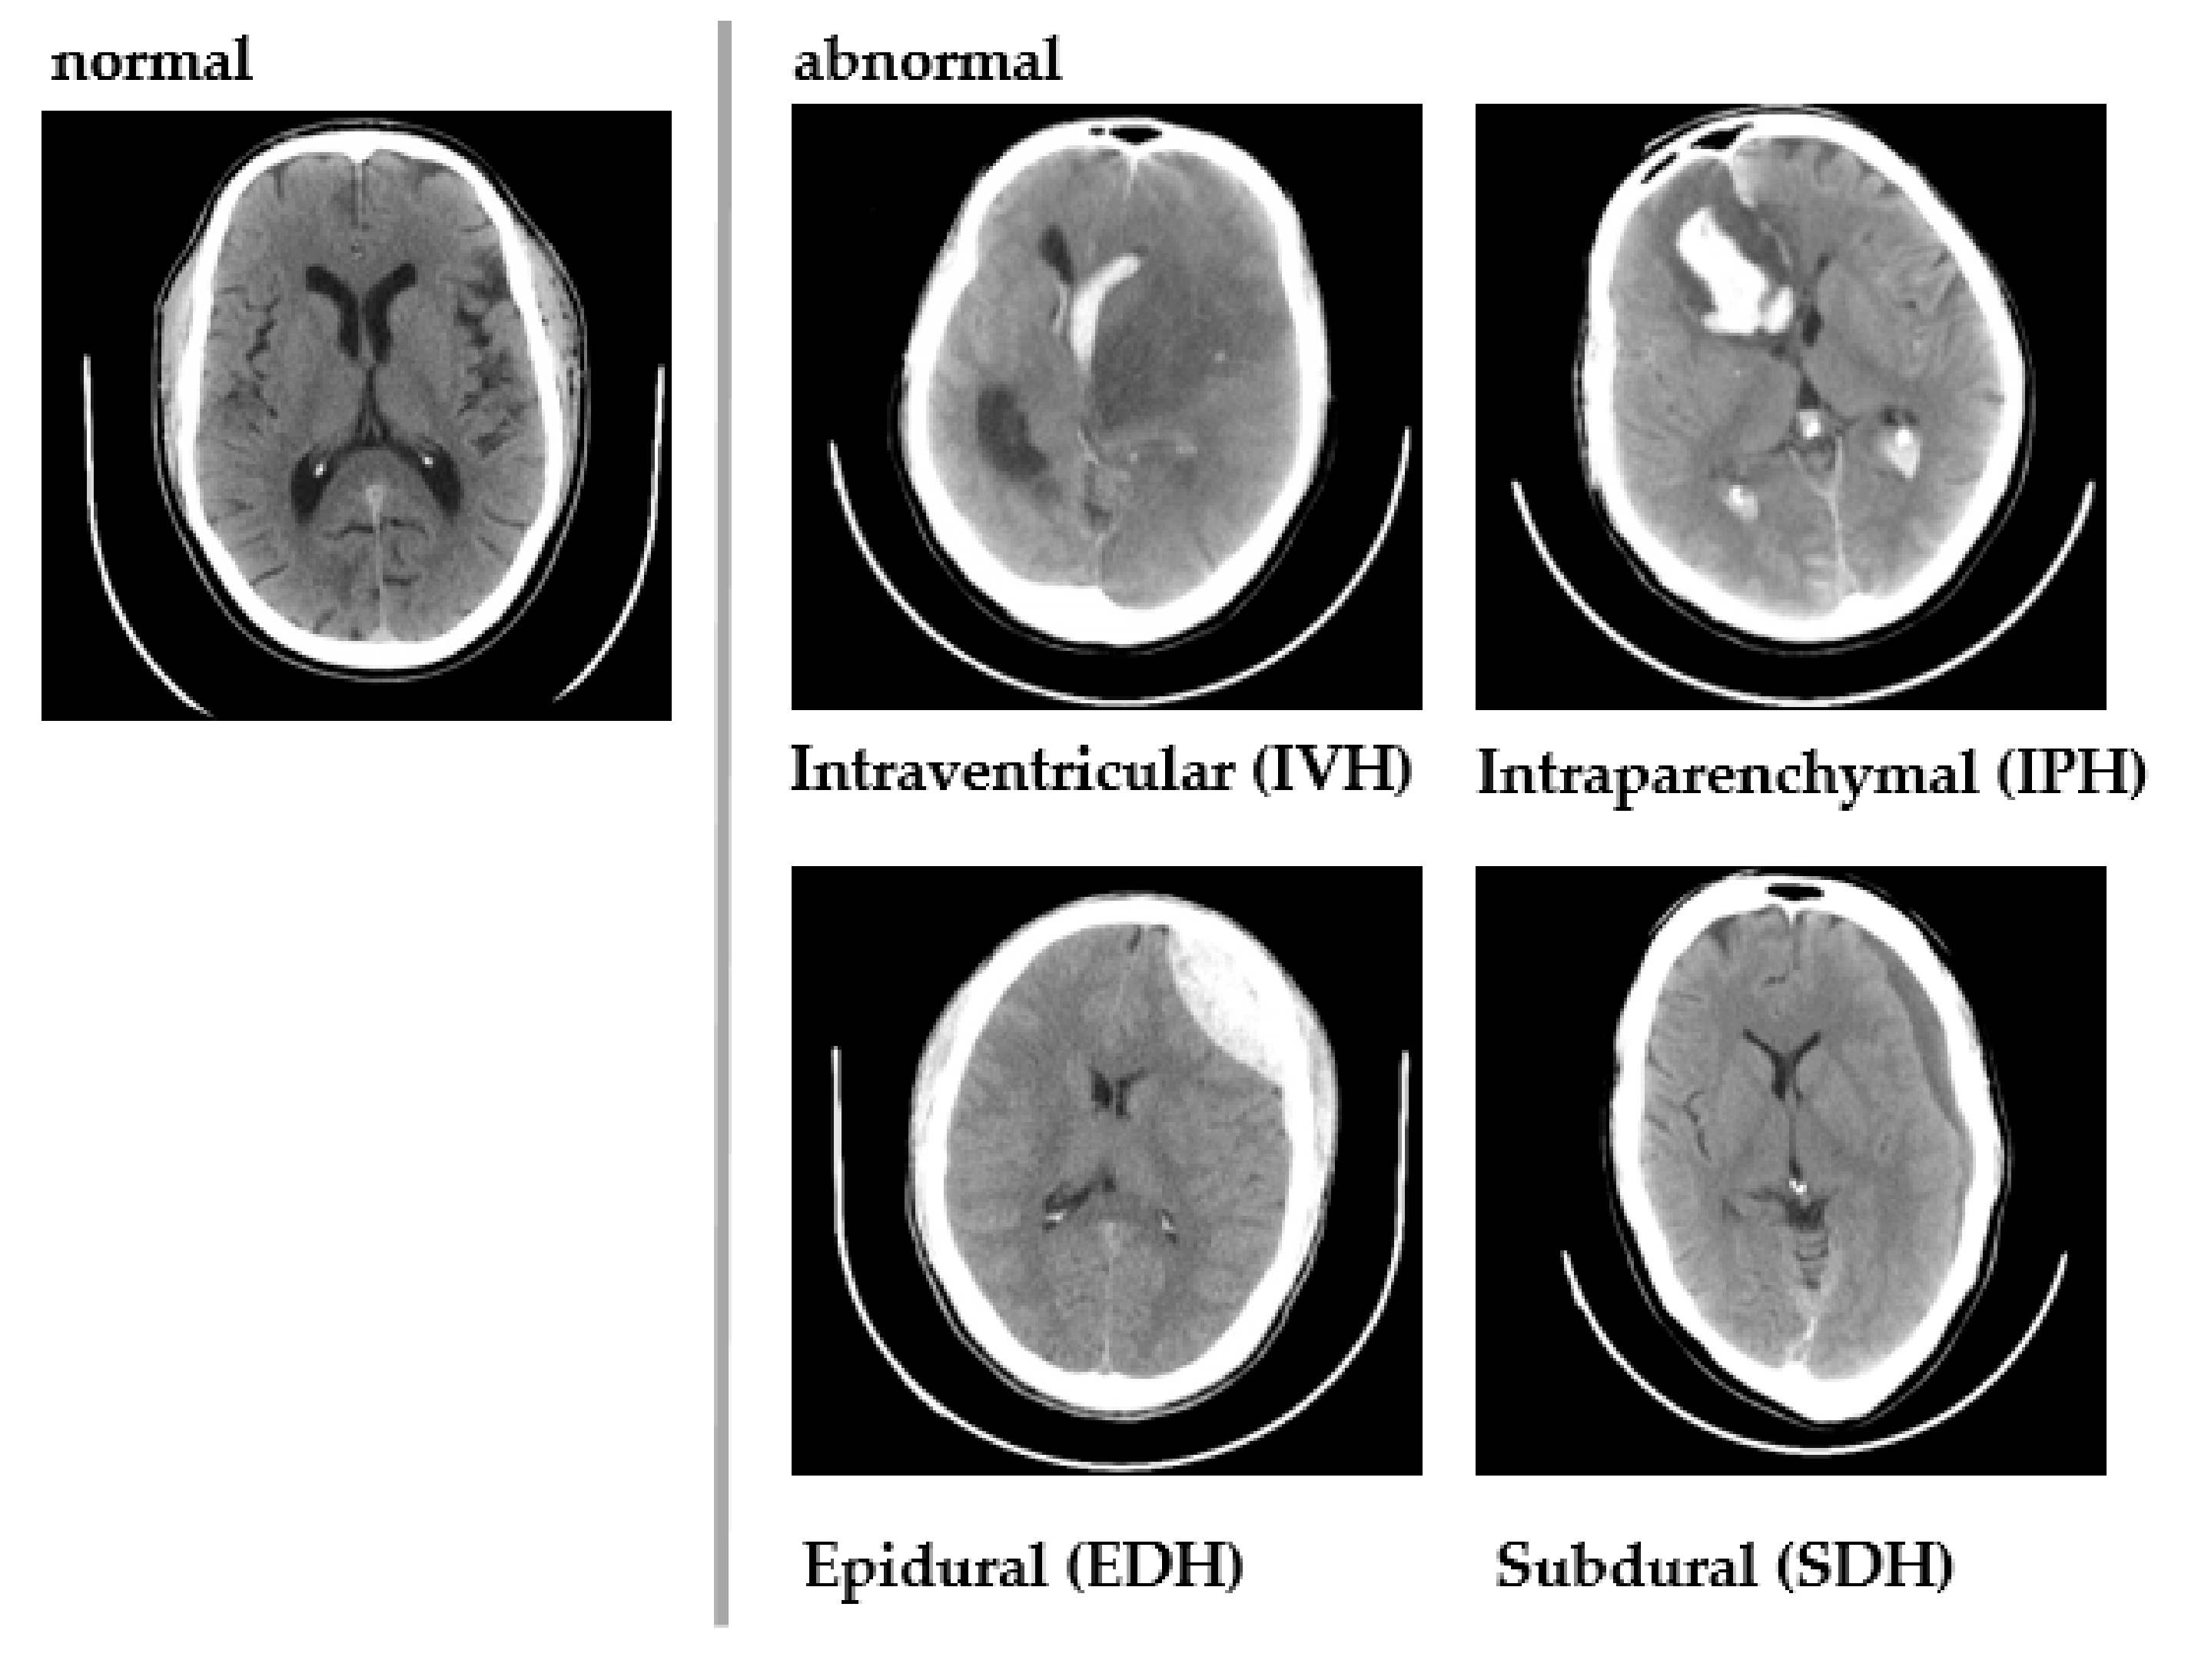

1. Introduction

4. Generics of Computer Aided Diagnosis

4.6. Deep Learning for Hematoma Detection